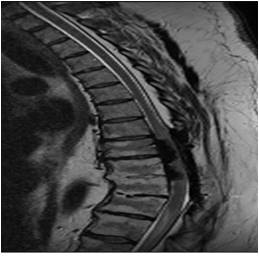

Idiopathic Hypertrophic Pachymeningitis

A chronic progressive diffuse inflammatory fibrosis of the dura mater. Diagnosis of exclusion since meningioma, lymphoma, sarcoid and TBc can present in a similar fashion. MRI findings of low signal intensity mass extending over several levels with linear or nodular peripheral enhancement (representing active inflammation) highly suggestive of the diagnosis. [ Article ]

chronic myelopathy with several decompressions

Courtesy Jay A Kaiser MD